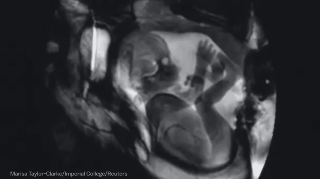

6. Un feto en el interior de su madre.